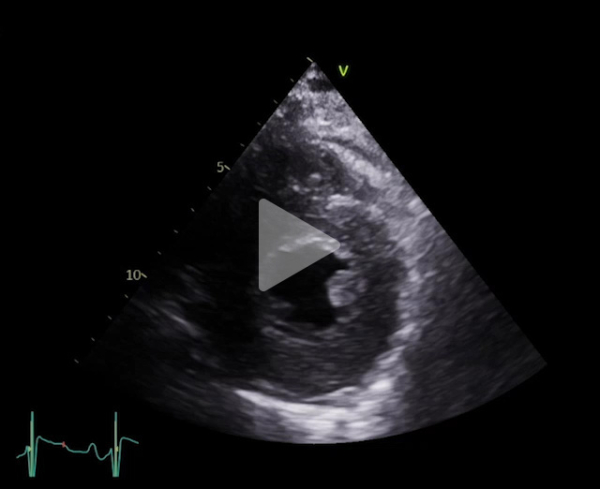

Vidéo 1

FEVG 40% en Simpson biplan, 45-50% visuellement. GLS -7%. Hypokinésie des bases et hyperkinésie de l'apex. VG non dilaté (DTDVG = 35mm, VTDVG =54ml/m2), hypertrophié (SIV = 18.5mm, PPVG = 19mm).

- DC = 3l/min, IC = 1.6l/min/m2 avec CCVG = 21mm et ITV sous Ao = 8cm

- OG dilatée à 40mL/m² (21cm2). OD dilatée à 19cm2

- Valve aortique tricommissurale, fine, pas de sténose ou fuite. Valve mitrale épaissie, pas sténose ou fuite

- Profil mitral restrictif, pressions de remplissage VG élevées (E/A =2.6, E/e’ moy = 22)

- Cavités droites non dilatées (Anneau tric =35mm)

- Fonction VD altérée (TAPSE = 7.7mm, S tric = 5.9cm/s)

- PAPS estimée sur IT modérée à 30 + 15mmHg (TAP 82ms)

- VCI dilatée ( 22mm), non compliante

- Lame péricardique minime